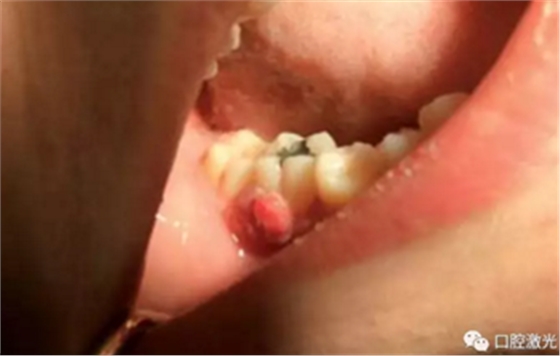

龈瘤指的是任何位于牙龈部的良性纤维瘤病变。龈瘤通常呈粉红色,虽然为良性,但会随牙龈一同生长,有时会因体积过大而包裹一颗或多颗牙齿。目前,龈瘤的具体病因上不可完全清楚,一般采用外科手术切除是被认为是安全的,其中就包含利用口腔激光进行切除。口腔激光拥有许多的波长,都可以用到龈瘤切除等软组织手术中,并且拥有快速凝固和高效灭菌的特点。

本文收集了多位年龄在14至50岁的龈瘤患者,均活检诊断后确认。所有手术均在门诊完成,全部使用半导体口腔激光。其功率设置为:4至6W,连续模式。光纤芯径300微米。所有的患者都在术后1周,4周,6个月以及1年时间复诊,评估激光手术的长期效果。

在治疗前,患者、医生及助手均佩戴正确的防护眼镜,并且对患处进行拍照记录。随后使用2%的利多卡因 1cc进行浸润麻醉。激光器设置完毕后,采取外切的手法,利用镊子将龈瘤拉伸后,从其根部进行外切。手术后无需缝针,并对切除物进行病理学检查。检查结果确认为纤维瘤。整个手术过程通常为4至6分钟。建议患者术后冰敷以减少水肿发生。